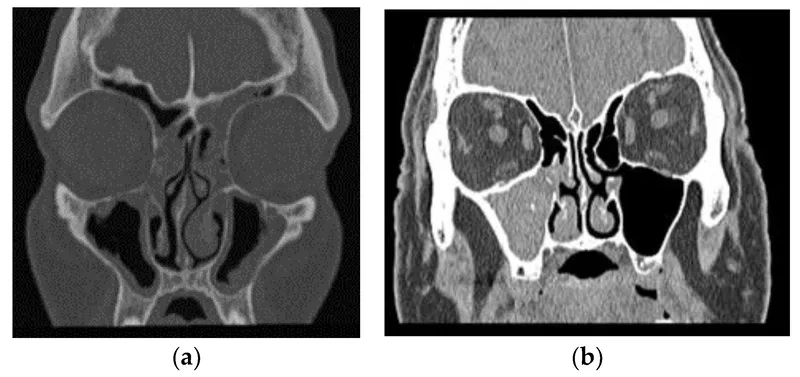

Image of the disease chronic sinusitis and other variables